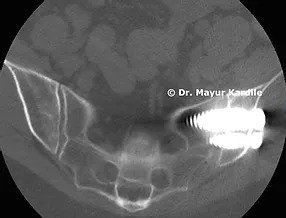

A 55-year-old lady complained of chronic low back radiating to left buttock pain for 6 years. Her pain was so severe that it didn't even allow her to roll in bed or climb upstairs without discomfort. Her life was clearly limited due to this pain.

A clinical diagnosis of SI joint dysfunction was made. Not having relief after two SI joint injections, she was advised Minimally invasive (MIS) SI joint fusion surgery.

MIS SI joint fusion is done through a 3 cm incision in the buttock area. In carefully selected patients, this procedure can give gratifying results.